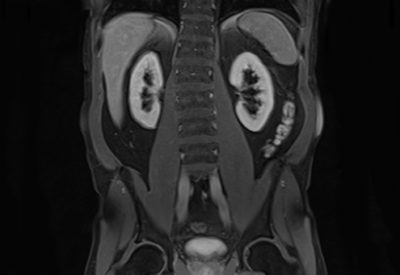

Hochwertige MRT-Untersuchung für maximale Diagnosesicherheit

Dann sind Sie bei uns richtig! Wir bieten Ihnen ein erfahrenes und spezialisiertes Ärzteteam, das MRT-Untersuchungen mit moderner Gerätetechnik durchführt. Unsere MRT-Untersuchungen sind optimiert und liefern hochauflösende Bilder, die eine maximale Diagnosesicherheit bieten.

Hochwertige MRT-Untersuchung für maximale Diagnosesicherheit

Dann sind Sie bei uns richtig! Wir bieten Ihnen ein erfahrenes und spezialisiertes Ärzteteam, das MRT-Untersuchungen mit moderner Gerätetechnik durchführt. Unsere MRT-Untersuchungen sind optimiert und liefern hochauflösende Bilder, die eine maximale Diagnosesicherheit bieten.